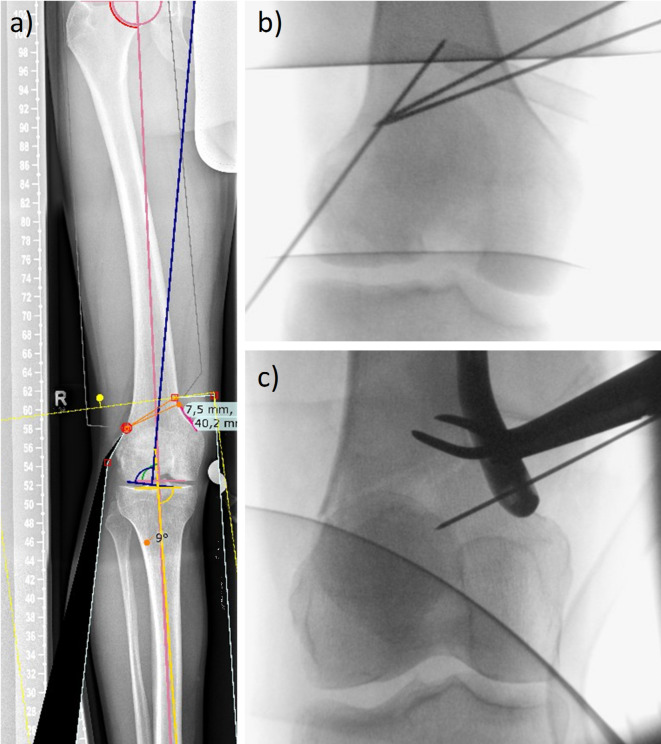

股骨远端截骨采用内侧闭合楔形手术,通过纠正冠状面错位来矫正膝外翻。该手术包括术前计划、楔形切口、截骨术以及用钢板和螺钉固定。然而,楔子关闭过程中的铰链裂缝存在重大挑战,通常需要进行修复。当代的解决方案已经探索了k-钢丝的使用,本研究调查了它们的生物力学意义。k线插入角度和直径之间的相互作用,在现有文献中经常被忽视,是其成功截骨效果的关键决定因素,突出了我们对这些关键参数的理解差距。我们假设k线的力学随插入角和直径的变化而变化。本研究采用基于计算机断层扫描的有限元模型,研究了不同角度(30°、45°和60°)和直径(1.6、1.8和2mm)的k针的引入,以评估股骨内侧闭合楔形截骨术的结构完整性。研究结果显示了角度相关的应力变化,60°配置显示出有利于减少拉伸和压缩载荷以及塑性变形的模式,这对于防止铰链断裂至关重要。直径变化显示应力或系统刚度没有显著差异。还发现,虽然角度对应力有显著影响,但只有在大角度的情况下,小直径才显得最优。与naïve模型的对比分析表明,60°角的k钢丝可以降低拉伸和压缩载荷以及塑性变形体积分数,从而降低断裂风险。这项研究强调了优化k线放置和配置的重要性,特别是强调了插入角度的重要性。未来的研究应扩大测试角度和直径的范围,并检查不同的股骨几何形状和截骨角度,以提供更全面的认识和加强临床应用。

Medial closing-wedge surgery for distal femoral osteotomy is employed to correct genu valgum by correcting coronal plane malalignment. This procedure involves pre-surgery planning, creating a wedge incision, performing the osteotomy, and stabilizing with plates and screws. However, hinge fractures during wedge closure present significant challenges, often necessitating revisions. Contemporary solutions have explored the use of k-wires, and this study investigates their biomechanical implications. The interplay between k-wire insertion angle and diameter, often overlooked in existing literature, is a critical determinant of their efficacy in achieving successful osteotomies, highlighting gaps in our understanding of these key parameters. We hypothesize that k-wire mechanics vary with insertion angle and diameter. This study examines the introduction of k-wires at different angles (30°, 45°, and 60°) and diameters (1.6, 1.8, and 2 mm) using computed tomography-based finite element models to assess structural integrity during femoral medial closing-wedge osteotomy. Results reveal angle-dependent stress variations, with 60° configurations exhibiting favorable patterns that reduce tensile and compressive loads and plastic deformation-crucial in preventing hinge fractures. Diameter variations show no significant differences in stresses or system stiffness. It was also found that while angle significantly affects stresses, lower diameters appear optimal only in combination with higher angles. Comparative analysis of k-wire systems with a naïve model demonstrates that k-wires at a 60° angle reduce tensile and compressive loadings and plastically deformed volume fractions, thus lowering fracture risk. This study underscores the importance of optimizing k-wire placement and configuration, particularly highlighting the significance of the insertion angle. Future research should expand the range of angles and diameters tested and examine different femoral geometries and osteotomy angles to provide a more comprehensive understanding and enhanced clinical application.